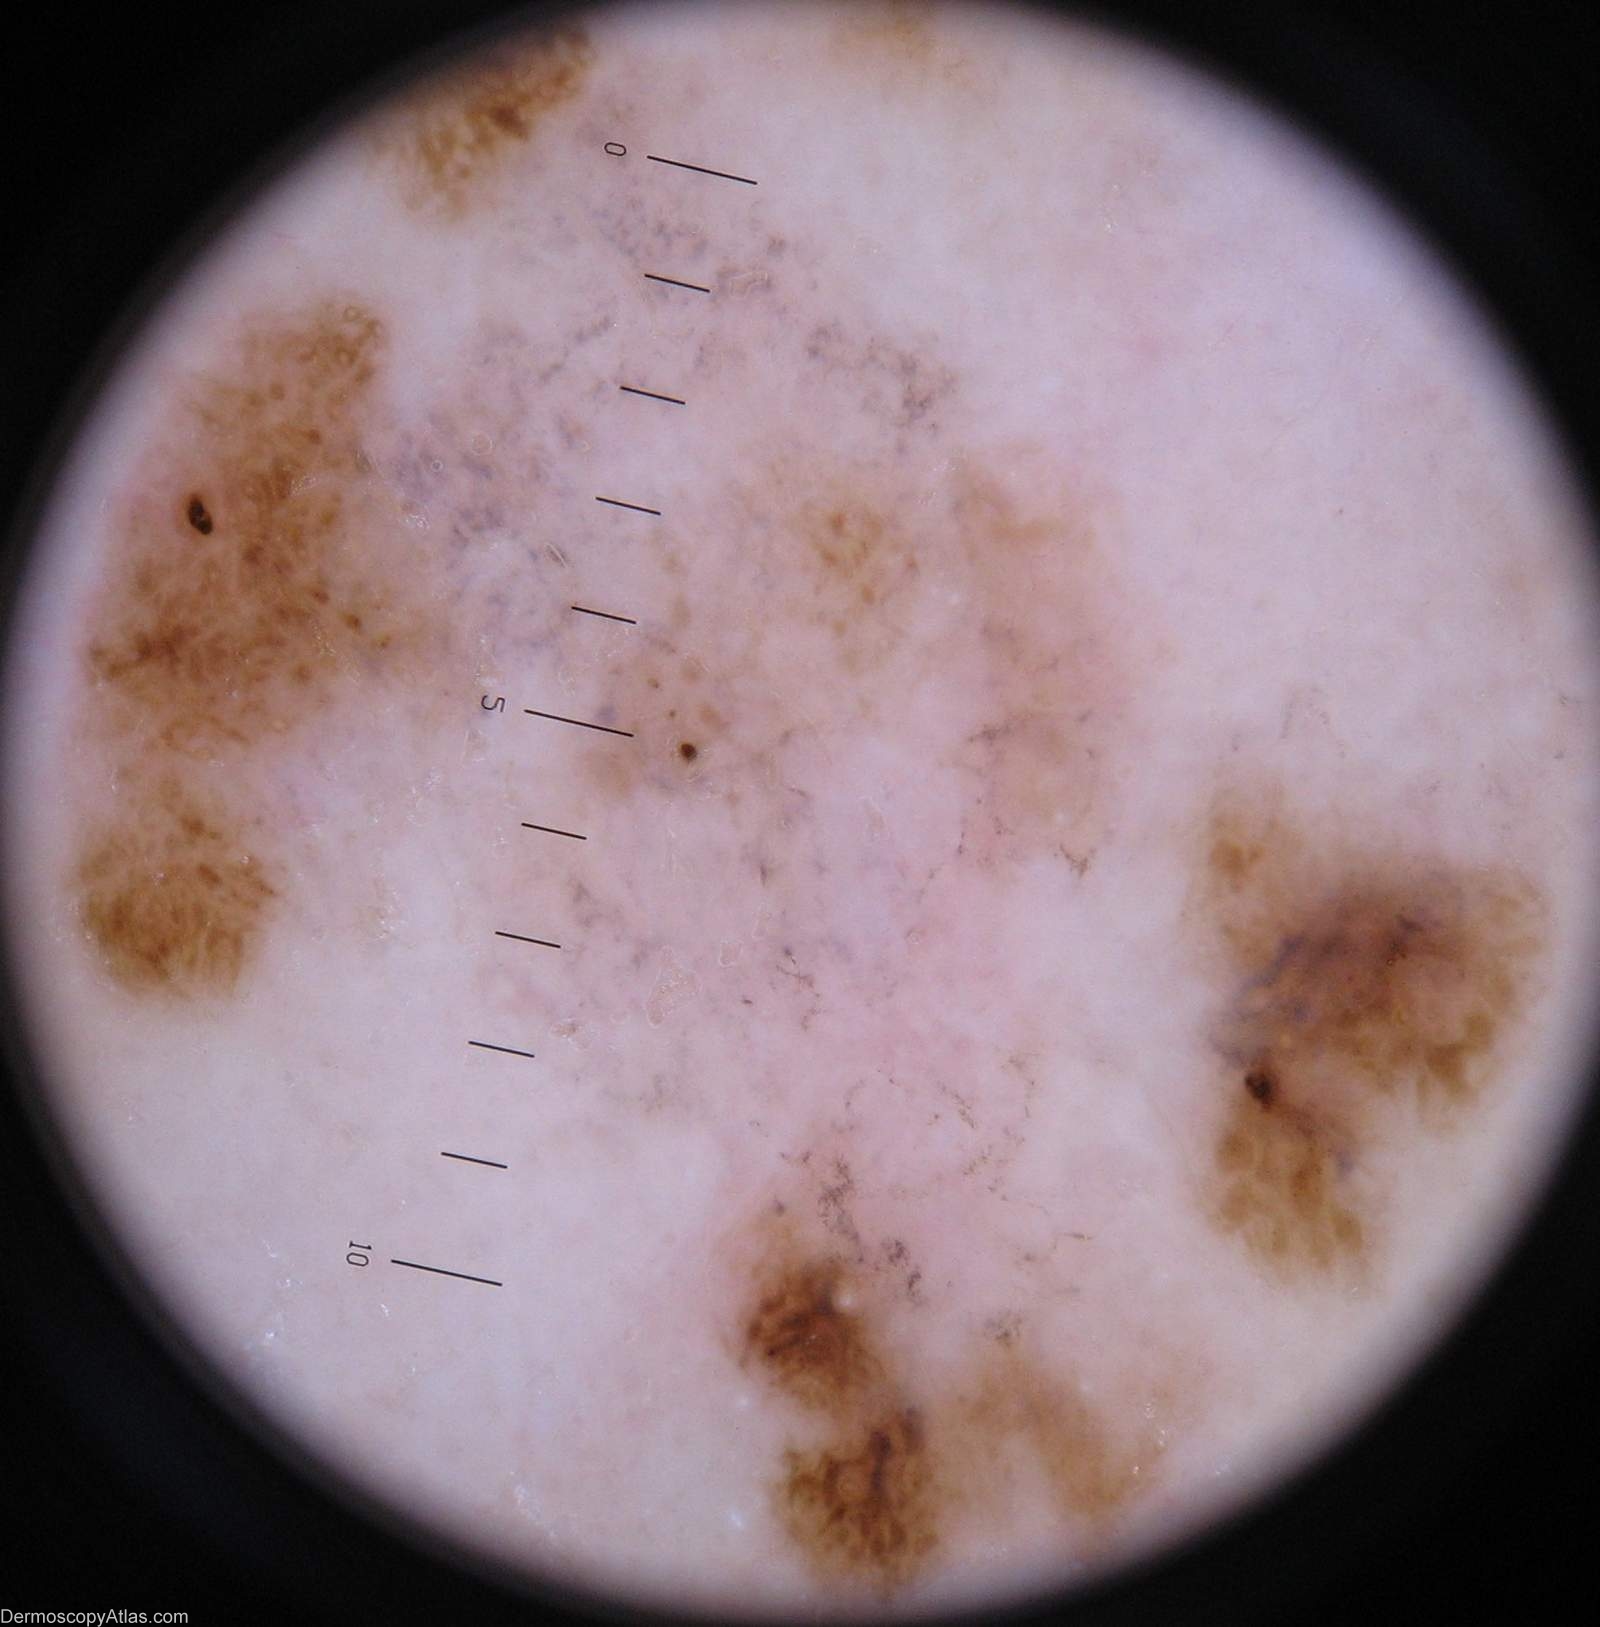

Image Number #2270 (Melanoma regression)

Site: Calf

Diagnosis: Melanoma regression

Description: Lesion on the calf. Clinically areas of regression are shown in both the pale and grey areas

Case courtesy of Dr Greg Canning  This poorly demarcated lesion is approx 5 cm in diameter and has resided on the left proximal postero medial calf of it's 72 year old owner for as long as she can remember. On reflection however she thinks it may have enlarged somewhat over the years. She has been repeatedly reassured about it by the doctors who have treated her numerous non melanoma skincancers.

Histopathology of incisional biopsy  There is an atypical melanocytic lesion composed of disparate foci separated by zones of regression. There are moderately to markedly atypical melanocytes forming irregular junctional nests and invading the epidermis. A lichenoid dermal inflammatory infiltrate is present and there are two foci of superficial nvasion of the dermis to the interface of papillary and reticular dermis. The Breslow thickness in each case is 0.4 mm. Mitoses are rare. The minimum clearance of the invasive components is 2.5 mm from the 3 o'clock margin. Atypical junctional nests almost abut the 3 o'clock edge.

The degree of regression obfuscates interpretation of the precursor lesion, but lentiginous activity is seen and involvement of a hair follicle. In combination with the multifocal nature of the lesion it

is likely that this is lentigo maligna melanoma.